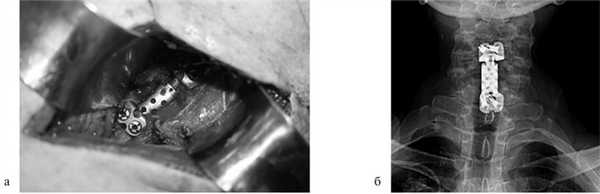

Для замещения удаленных позвонков у 8 (28%) больных применен сетчатый титановый протез «MASH» (рис. 1), который использовался нами с 2006 по 2010 г. Телескопическая система эндопротезирования, которая использовалась с 2010 по 2016 г., применена у 21 (72%) пациента (рис. 2). Спондилодез при помощи пластин выполнен у 19 (65,5%) больных, комбинированная стабилизация (титановые винты и пластины) — у 10 (34,5%) пациентов.

Рис. 2. Корпорэктомия позвонка СV с замещением дефекта раздвижным эндопротезом тела позвонка. а — интраоперационная фотография; б — послеоперационная рентгенограмма шейного отдела позвоночника.